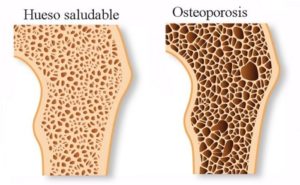

También al eliminar el exceso de calcio de las arterias, el organismo lo aprovecha para remineralizar el hueso, en promedio el aumento de masa ósea en un año es del 15%.